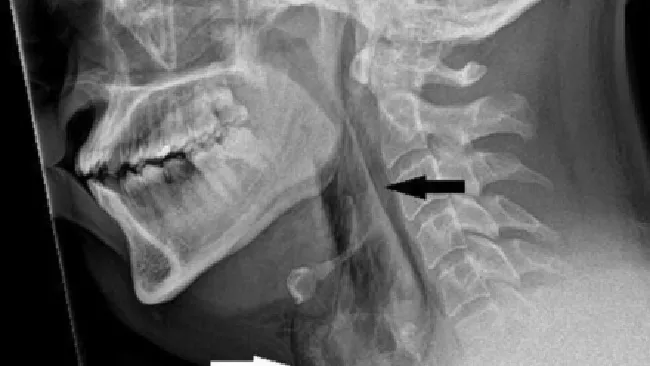

Hasil rontgen leher menunjukkan pria tersebut mengalami emfisema bedah. Kondisi saat udara terperangkap di bawah lapisan jaringan terdalam di bawah kulit.

Selain itu, dari hasil pemindaian tomografi komputer (CT) ditemukan ada robekan yang terjadi di antara tulang ketiga dan keempat, atau tulang belakang, di lehernya. Udara juga terkumpul di ruang dada di antara paru-parunya.